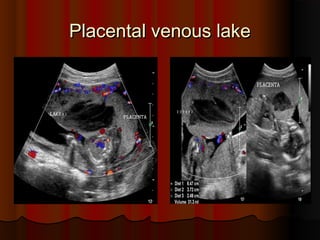

Placental venous lakePlacental venous lake

This placenta, in a 28 week pregnancy shows aThis placenta, in a 28 week pregnancy shows a

large hypoechoiclarge hypoechoic ((almost anechoicalmost anechoic)), measuring, measuring

5 x 3.5 cms5 x 3.5 cms.. in sizein size.. Some particulate matterSome particulate matter

was seen flowing through this area, which waswas seen flowing through this area, which was

closer to the fetal surface of the placentacloser to the fetal surface of the placenta.. TheseThese

ultrasound images suggest a typical appearanceultrasound images suggest a typical appearance

of a large venous lake in the placentaof a large venous lake in the placenta.. ColorColor

Doppler image showed no major flow patternDoppler image showed no major flow pattern

within this placental lakewithin this placental lake.. The fine, echogenicThe fine, echogenic

strands within the lesion appear to be nothingstrands within the lesion appear to be nothing

more than artefacts produced by slow flowingmore than artefacts produced by slow flowing

blood within the lesionblood within the lesion..

Placental venous lakePlacentalvenous lake This placenta, in a 28 week pregnancy shows aThis placenta, in a 28 week pregnancy shows a large hypoechoiclarge hypoechoic ((almost anechoicalmost anechoic)), measuring, measuring 5 x 3.5 cms5 x 3.5 cms.. in sizein size.. Some particulate matterSome particulate matter was seen flowing through this area, which waswas seen flowing through this area, which was closer to the fetal surface of the placentacloser to the fetal surface of the placenta.. TheseThese ultrasound images suggest a typical appearanceultrasound images suggest a typical appearance of a large venous lake in the placentaof a large venous lake in the placenta.. ColorColor Doppler image showed no major flow patternDoppler image showed no major flow pattern within this placental lakewithin this placental lake.. The fine, echogenicThe fine, echogenic strands within the lesion appear to be nothingstrands within the lesion appear to be nothing more than artefacts produced by slow flowingmore than artefacts produced by slow flowing blood within the lesionblood within the lesion..